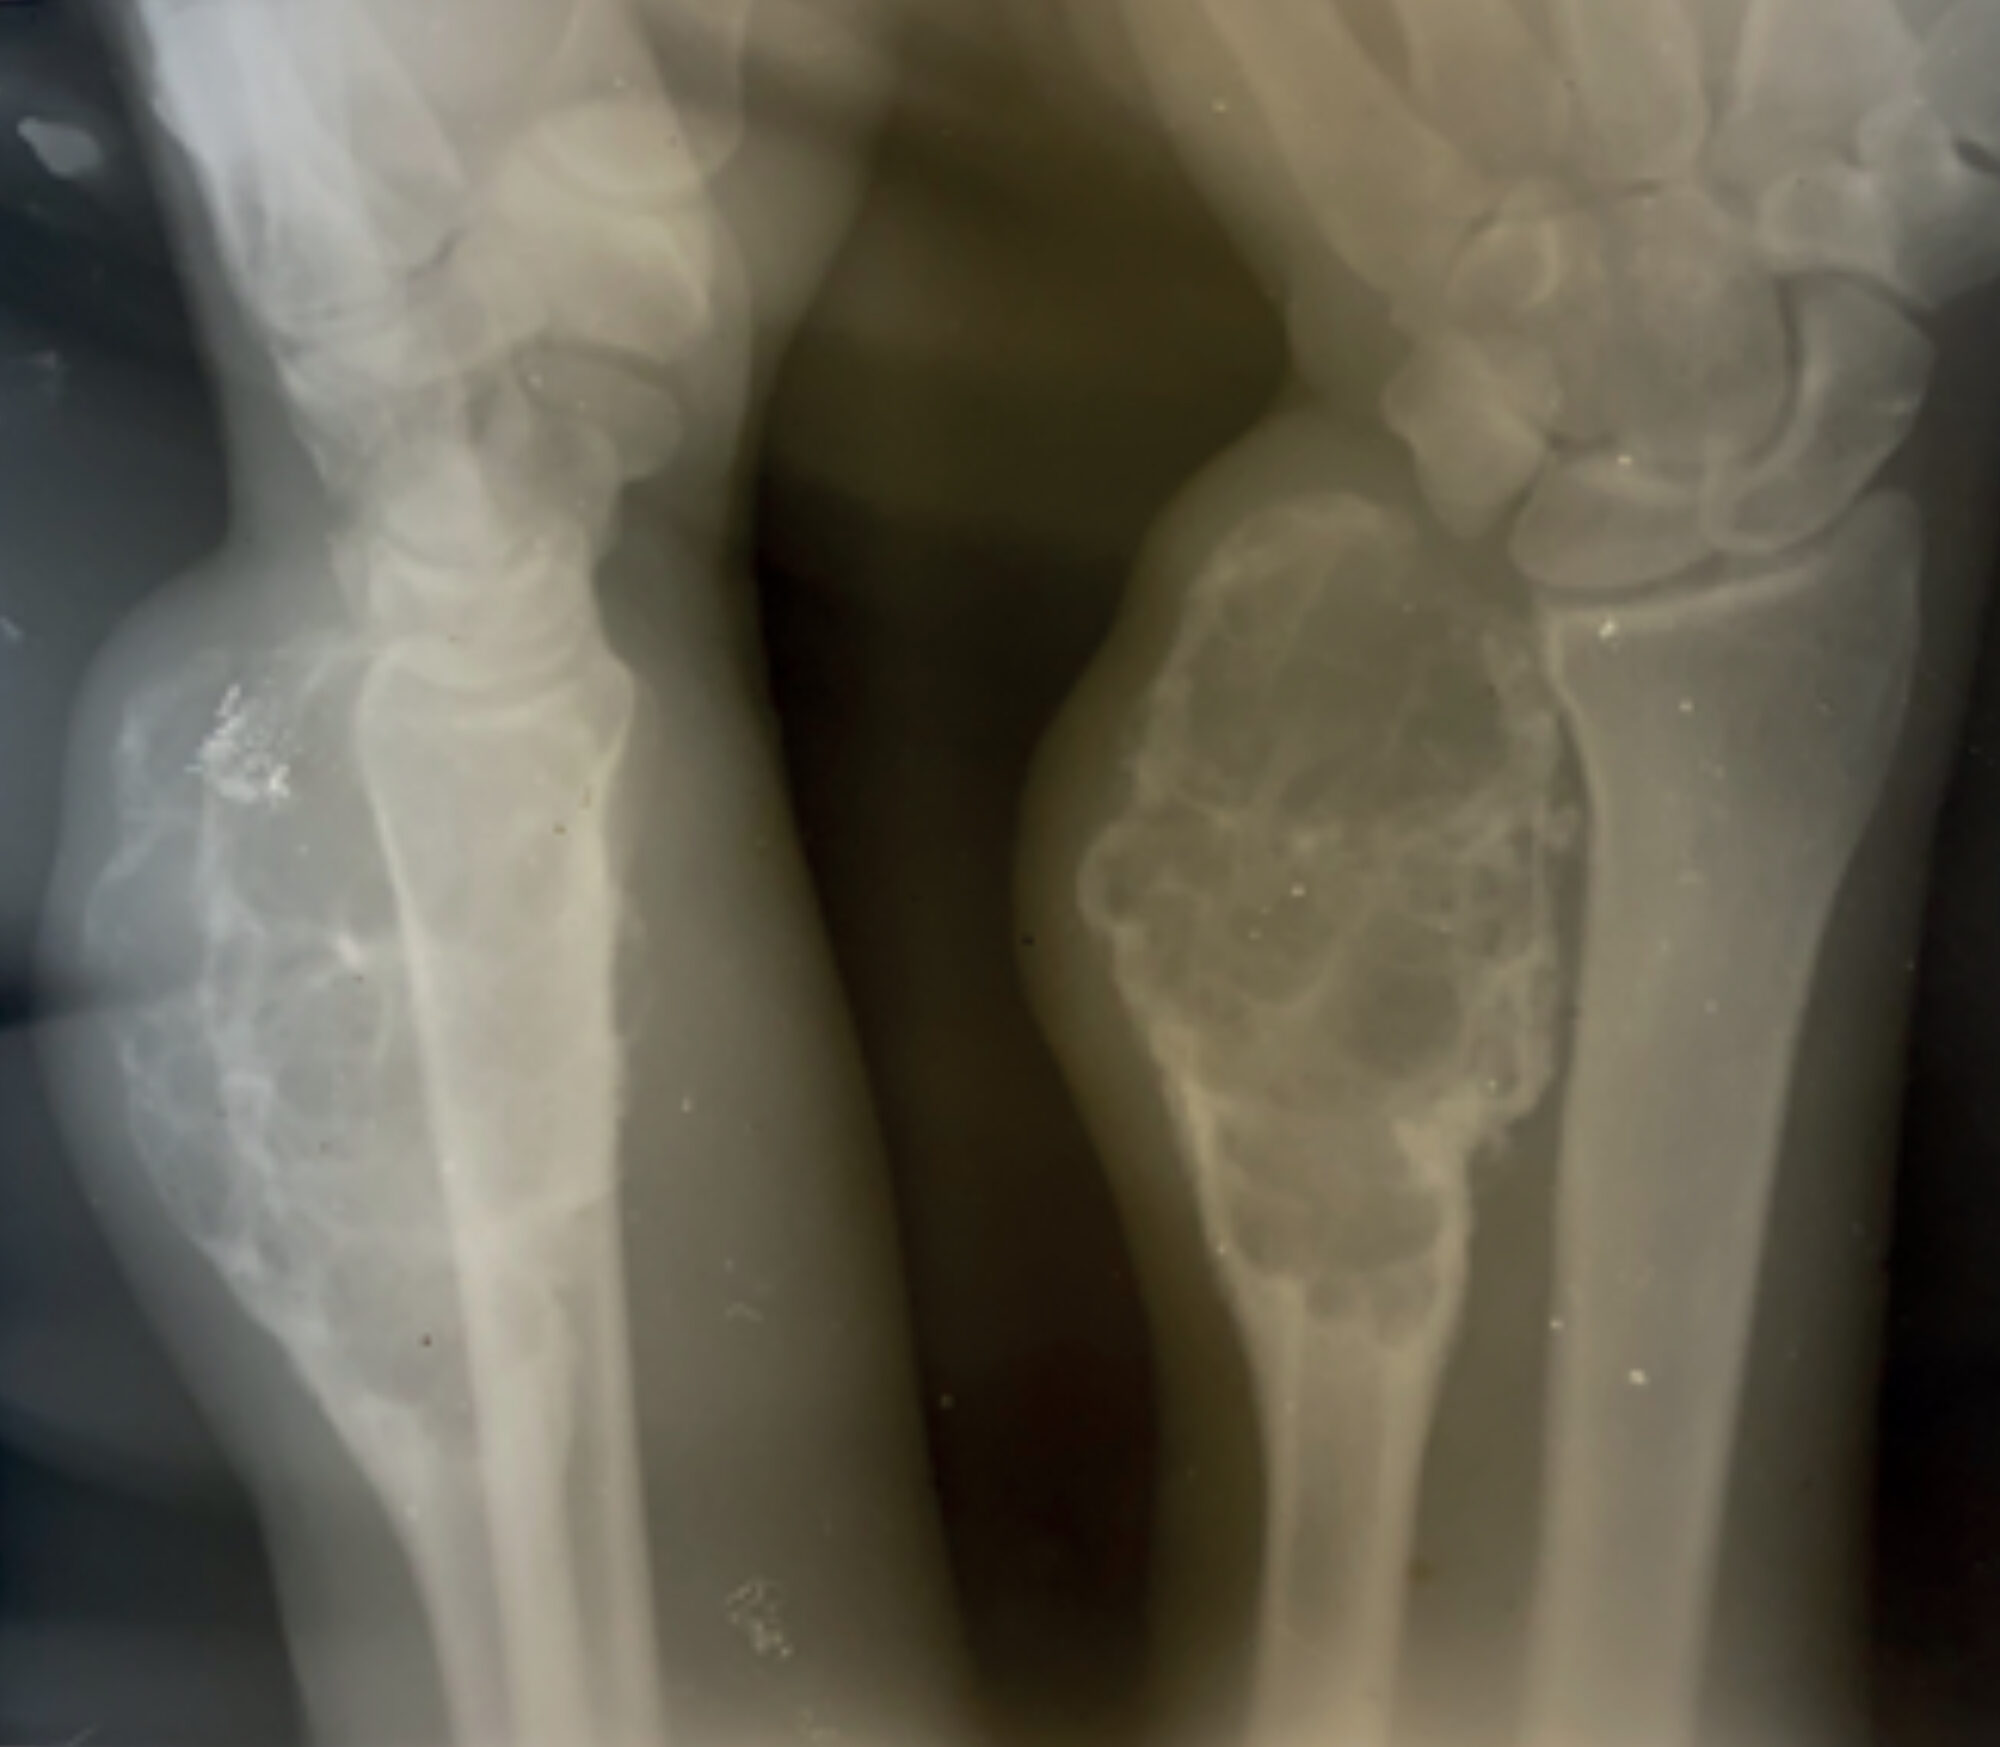

| Case A 23-year-old man presents at the hospital with a swelling of the right wrist (Figure 1). It originated a few months earlier and slowly increased in size. It was not preceded by any trauma. On clinical examination a round, hard swelling with varying surface is palpable on the ulnar side of the right wrist. No enlarged lymph nodes can be palpated. An X-ray of the wrist shows an expansive lytic lesion of the distal ulnar bone of the right wrist (Figure 2). A chest X-ray was performed and showed no abnormalities. A biopsy was not performed right away because of lack of the patient’s financial means and because there is only one pathologist in the whole country. Based on the clinical findings and x-ray the medical team made a differential diagnosis of an osteosarcoma or benign bone cyst and consulted the Consult Online panel for help. On clinical examination a round, hard swelling with varying surface is palpable on the ulnar side of the right wrist. The swelling does not feel warm, and the function of the hand is normal. |

GCTB usually occurs after the closing of the epiphyseal plates and mostly affects young adults between the age of 20-40.[1,3] Described by the radiologist of the consult online panel as: An expansive bone lesion of (unknown) cm in the distal ulna, with a predominantly osteolytic matrix, some ground glass areas and no obvious calcifications. Some thin septae and cortical thinning is seen. Females are slightly more often affected than males.[1,2,3] An occurrence of the disease before the age of 20 is uncommon. The disease most often presents solitary, although multicentric GCTB has been seen in younger individuals.[1] Risk factors of the disease and the exact pathogenesis is not yet fully understood.[1]

Described by the radiologist of the consult online panel as: An expansive bone lesion of (unknown) cm in the distal ulna, with a predominantly osteolytic matrix, some ground glass areas and no obvious calcifications. Some thin septae and cortical thinning is seen.